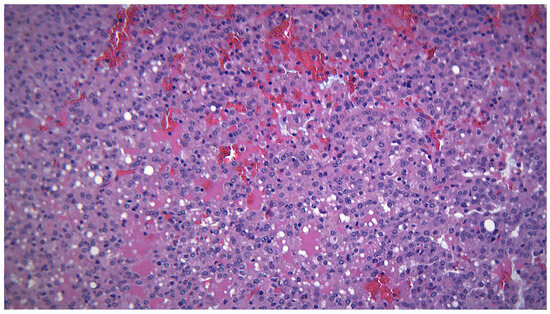

3.1. Warthin Tumor

3.5. Granulomatous Pathology